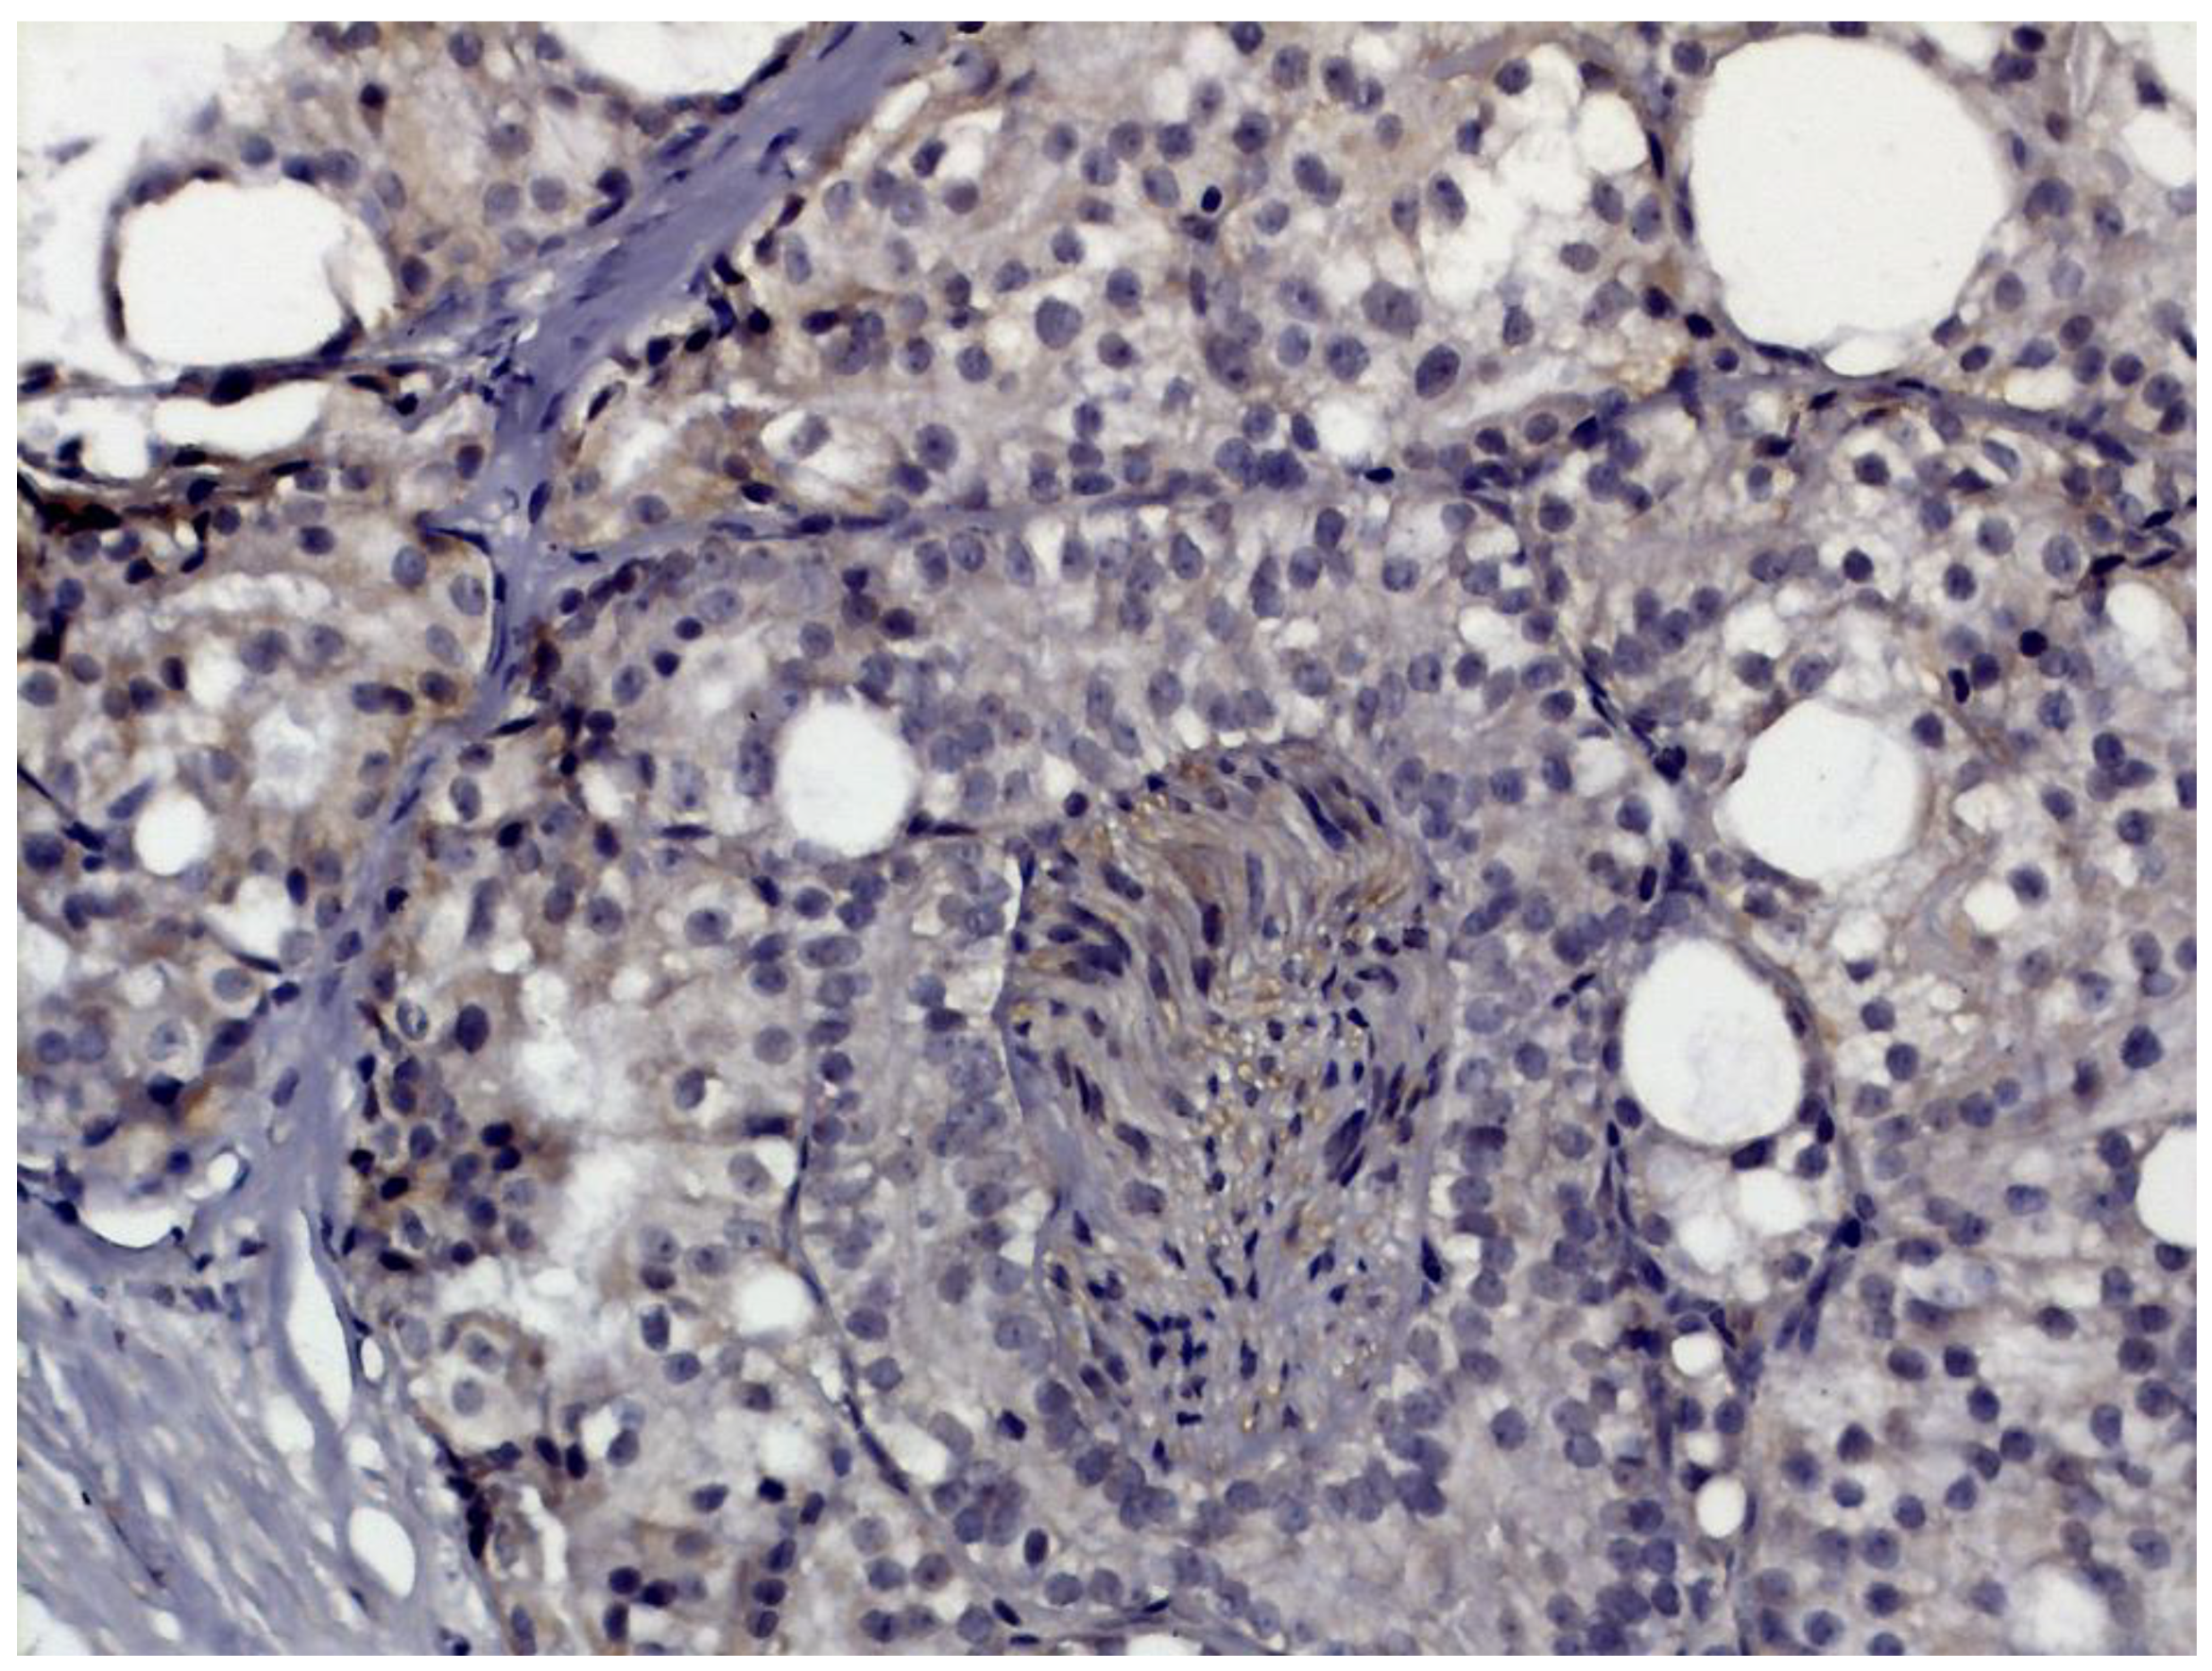

- Renal cell carcinoma

- Sun, L.; Zhang, Z.; Zhao, H.; Qiu, M.; Wen, Y.; Yao, X.; Tang, W.H. Identification of TRPM2 as a marker associated with poor prognosis and immune infiltration in kidney renal clear cell carcinoma. Front. Mol. Biosci. 2022, 8, 774905. [Google Scholar] [CrossRef]